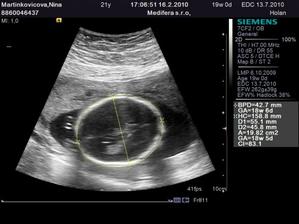

♥ 16.2. (utorok) ideme na 4D ultrazvuk!! 🙂 - Boli sme, nádherný zážitok!!! Je to chlapec ako sa patrí, úplne zdravý a krásny!!! 🙂 4D nám lekár ukázal len nožičky a pipíka, lebo tvárička nie je dobre vidieť tak skoro, ale to vôbec nevadí... 🙂